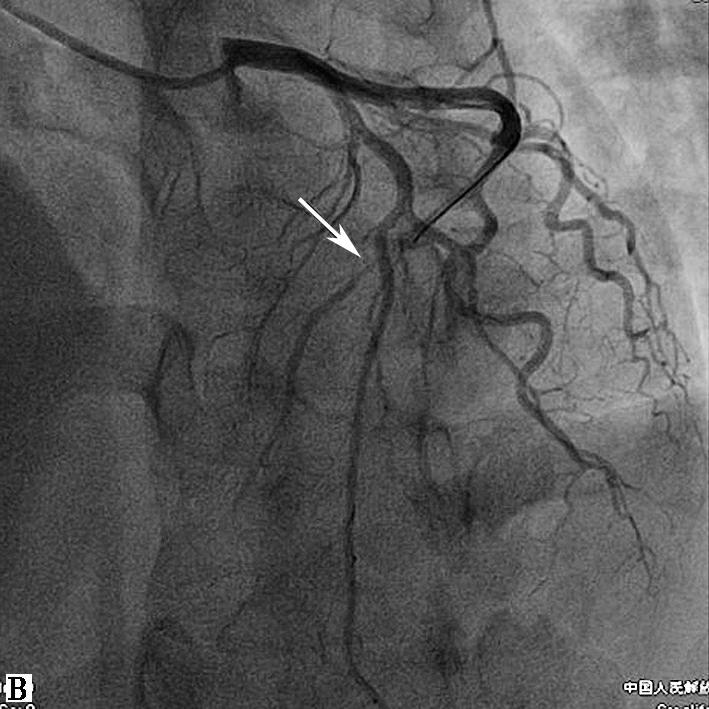

患者男性,34岁,主因胸闷憋气3周余于2015年12月22日入院。患者于2015年11月25日午餐后突然出现胸骨后憋闷、疼痛,呈压榨性,伴烦躁、大汗、恐惧,症状持续不能缓解,急诊至当地县医院,心电图提示:V2~V5导联ST段弓背向上抬高,诊断为“急性前壁心肌梗死”,给予阿司匹林300mg、氯吡格雷片600mg顿服,即刻向上级医院转诊;11月25日15点52分转入当地市医院,测血压70/40mmHg,给予多巴胺泵入,急查心肌酶升高,心电图提示:Ⅱ、Ⅲ、aVF及V2~V5导联ST段弓背向上抬高,诊断为“急性下壁、前壁心肌梗死”,于当日17时行急诊PCI手术,冠脉造影(图1)提示:左优势型,LAD开口完全闭塞,LCX粗大,远段完全闭塞,RCA未见明显狭窄,术中出现心源性休克,给予植入IABP支持,并给予LAD球囊扩张+血栓抽吸,LAD前向血流恢复TIMI 3级。术后常规抗凝、抗血小板治疗,血压稳定后给予拔除IABP(具体不详)。患者自觉症状未见好转,仍有胸闷,憋气,体力明显受限,为进一步诊治入我院。

图1当地心电图及急诊PCI结果

A.当地市医院急诊心电图提示:Ⅱ、Ⅲ、aVF、V2~V5导联ST段弓背向上抬高;B.急诊造影提示:LAD开口闭塞,回旋支远段栓塞;C.PCI术后,LAD TIMI 2级,LCX远段血流未恢复